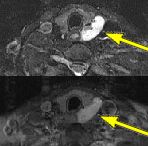

Fig.1 Fig.2 Fig.3 Fig.4

FINDINGS: The ultrasound (not shown) revealed a large solid mass behind the left lobe of the thyroid. Fig. 1-2 are MRI images of the neck demonstrating a mass behind the left thyroid lobe with hyperintensity on T2 weighted and STIR images (Fig. 1, 2 top) and enhancement higher than the thyroid (Fig. 2 bottom). Fig. 3-4 are Sestamibi images with Fig. 3 being coronal (top) and axial (bottom) SPECT images and Fig. 4 the early and delayed static images demonstrating persistent activity in the mass on delayed images while the thyroid activity washes out (arrows).